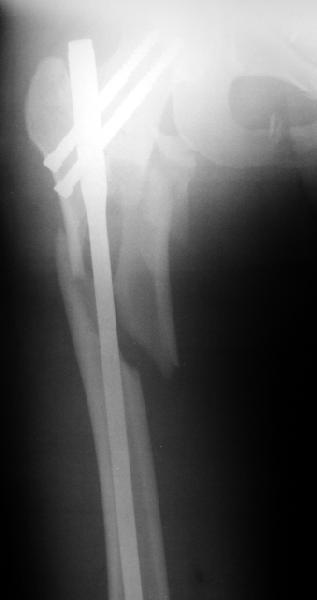

Спасибо, все практически так и получилось - на счастье в наших краях на днях была конференция по ожогам, на которую представители "Деоста" ехали на выставку. Попутно захватили нам реконструкционный гвоздик ChM с набором инструментов.

Оперировали вчера. Не сказать, что все прошло гладко - вертельная область была расколота и в сагиттальной, и во фронтальной плоскости, гвоздь попал в перелом и сместился кзади, что заметили уже после введения винтов, пришлось все извлечь и переставить. Снимки в приложении. Буду признателен за комментарии.

Если честно, мне не нравится стояние отломков

проксимального отдела. На мой взгляд причина в недостаточной осевой тракции сегмента перед этапом дистального блокирования. Если это действительно так, я бы попробовалудалить дистальные блокирующие винты, дать осевую тракцию(дистрактор, ортопедический стол, др.) и повторное дистальное

блокирование.

уважаемый А.Ч.! Не уверен, что отломки сопоставлены хорошо. Особенно плохо лбстоят дела с малым вертелом. Клинический исход по-видимому будет неудовлетворительным.